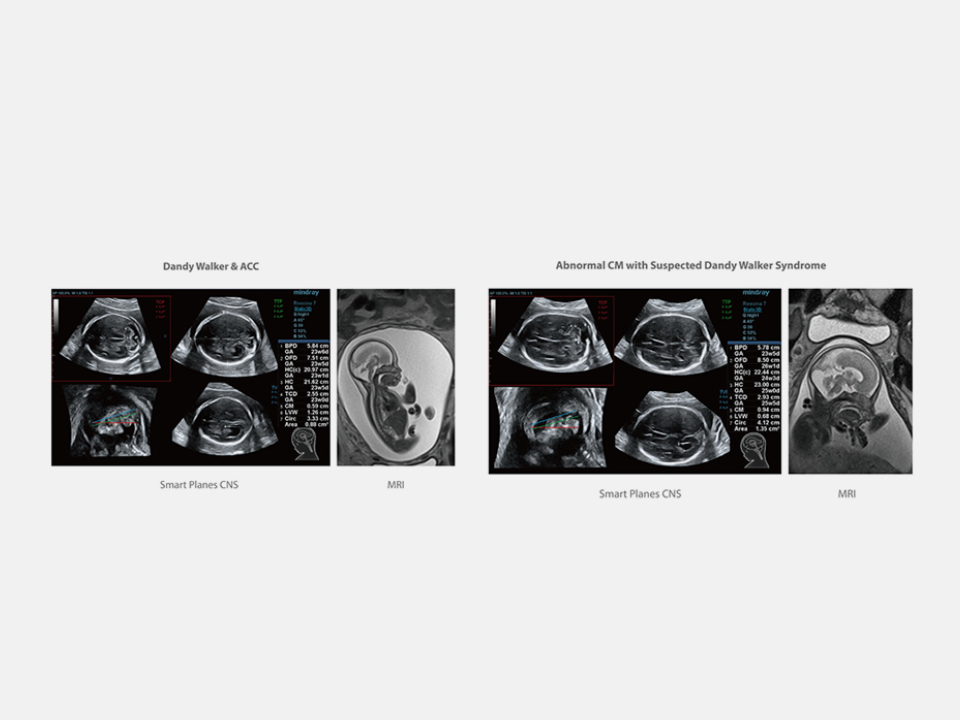

Thanks to the innovative, software-driven ZST+ platform, the Resona series is continuously evolving with the leading-edge technologies to meet the most challenging diagnostic demands in womenŌĆÖs health practice. More importantly, it is designed with the understanding that the wisdom of experts is always precious, and you need more intelligent partner for enhanced speed and confidence. Finally, Resona series with Zone Intelligence provides a total solution to help you with diagnostic confidence, efficiency, and standardization across different diagnostic challenges in todayŌĆÖs demanding and overburden hospital environment.